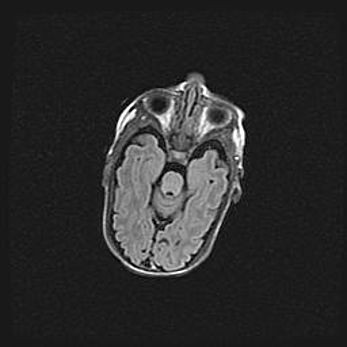

Лейкомаляция с кистозно-глиозной дегенерацией головного мозга.

Возраст: 2 месяца 25 дней

Вес: 6400 г

Окружность головы: 40 см

Срок гестации: 41 неделя

Лейкомаляцию относят к ишемически-гипоксическим повреждениям головного мозга, диагностируемым у новорожденных. При лейкомаляции в головном мозге обнаруживают очаги некроза, возникшие после тяжелой гипоксии и нарушения кровотока. В процессе морфогенеза очаги проходят три стадии: 1) развития некроза, 2) резорбции и 3) формирования глиозного рубца или кисты. Перивентрикулярная лейкомаляция (ПЛ) встречается примерно в 12% случаев среди новорожденных, обычно – у недоношенных детей, причем, частота ее зависит от массы, с которой младенец появился на свет. Наибольшее число малышей страдает лейкомаляцией, если масса при рождении 1500-2500 г.